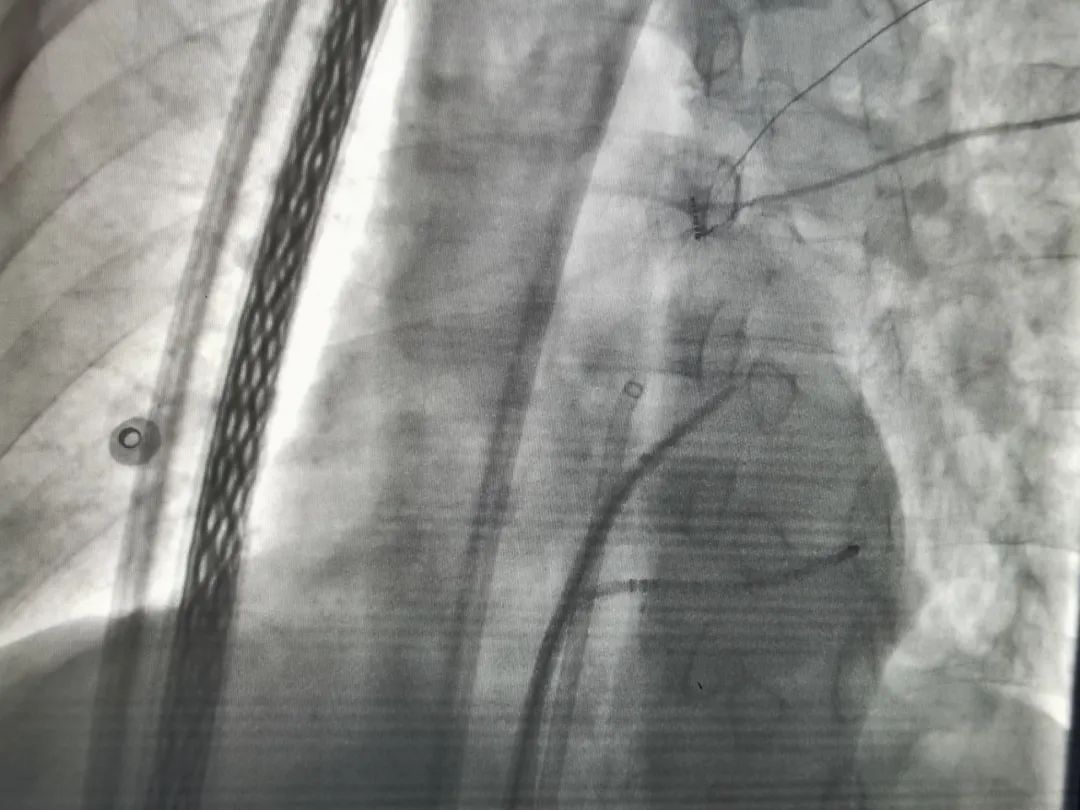

导丝游走,李枫教授和团队熟练地将导管送至上腔静脉行房间隔穿刺,完成肺静脉及左心房造影。在CARTO系统和肺静脉单环状标测电极(Lasso电极)联合应用下,标测肺静脉,采用冷盐水灌注导管进行双侧肺静脉前庭的环形消融,每2mm一个点逐个消融。从右肺静脉前壁开始,在CARTO系统引导下,环绕双侧肺静脉,从不同的三维角度,精准定位逐点消融。时间静静流淌,术者们始终一丝不苟,不知疲倦的手眼并用,鏖战数小时,最终完成消融环对接。随着最后一个点消融成功,心电监测屏幕显示Lasso电极上原来杂乱的肺静脉电位瞬间完全消失,肺静脉实现双向电学隔离,手术成功,术者们纷纷露出微笑。术后密切监护提示,郑师傅房颤均无发作,症状得到明显缓解。